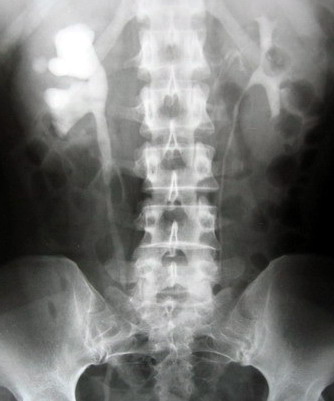

“感覺很好,都不痛了,真是謝謝你們!”7月5日,濰坊市市立醫(yī)院泌尿外科主任解魯明通過查看病房了解到患者趙先生的情況后,滿意地點(diǎn)了點(diǎn)頭。原來趙先生因患輸尿管結(jié)石于7月4日在濰坊市市立醫(yī)院做了局麻下急診輸尿管鏡手術(shù)。手術(shù)后不足一天時間,趙先生之前的結(jié)石之痛已經(jīng)完全消除。

該手術(shù)對于輸尿管中下段結(jié)石可在發(fā)病后快速進(jìn)行腔內(nèi)碎石,不用開刀,經(jīng)尿道碎石,無需特殊術(shù)前準(zhǔn)備,患者發(fā)病后可立即進(jìn)行手術(shù),直接將結(jié)石擊碎取出,甚至術(shù)后無需留置導(dǎo)尿管和輸尿管支架管,這樣避免了腰椎穿刺引起的腰痛及頭痛等腰麻的并發(fā)癥。術(shù)前、術(shù)后都無需禁食,對合并糖尿病的患者更好管理。術(shù)后無管化也避免了插管給病人帶來的疼痛不適。住院時間明顯縮短,一般術(shù)后48小時可出院,整個住院費(fèi)用減少1/3—1/2。手術(shù)效果可謂立竿見影,立即解除痛苦,該技術(shù)處于全國領(lǐng)先水平。針對輸尿管中下段結(jié)石,可作為一種常規(guī)手術(shù)方式進(jìn)行全面推廣。同時,濰坊市市立醫(yī)院泌尿外科目前還擁有全國最先進(jìn)的體外沖擊波碎石機(jī),德國進(jìn)口輸尿管鏡、經(jīng)皮腎鏡,瑞士進(jìn)口EMS氣壓彈道碎石機(jī)。歡迎廣大病友咨詢。